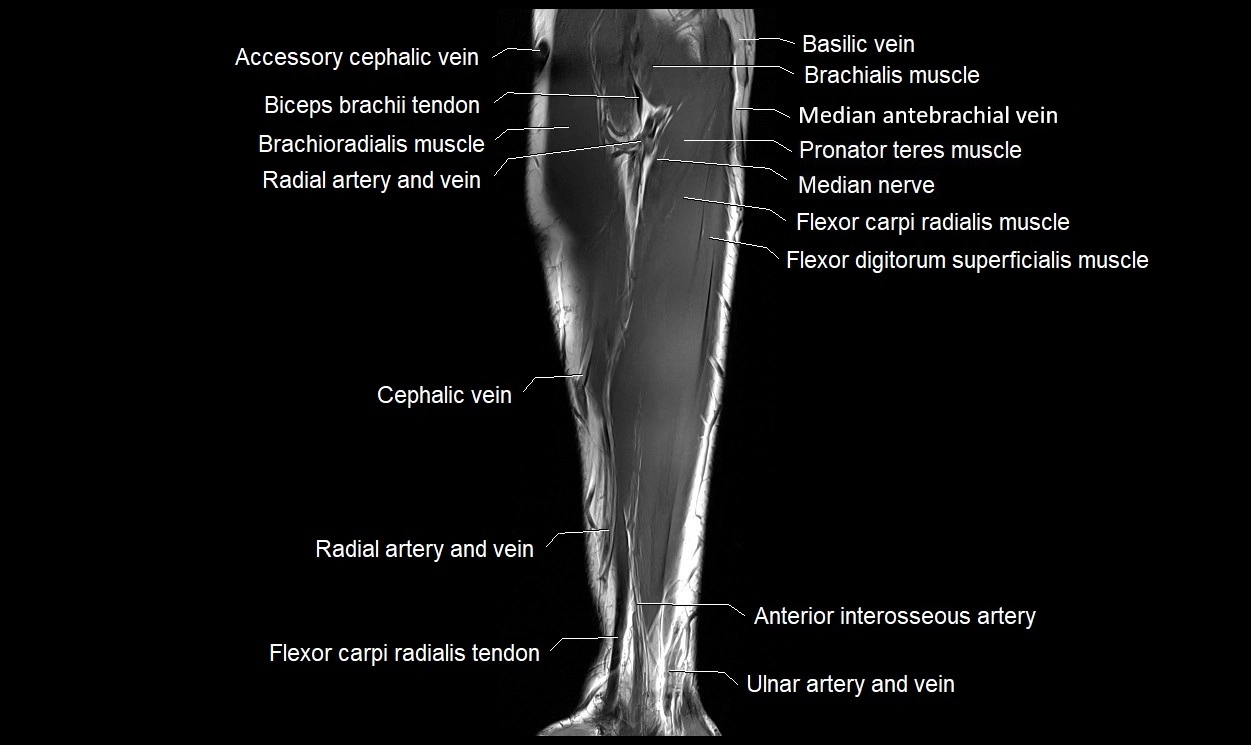

MRI images

image